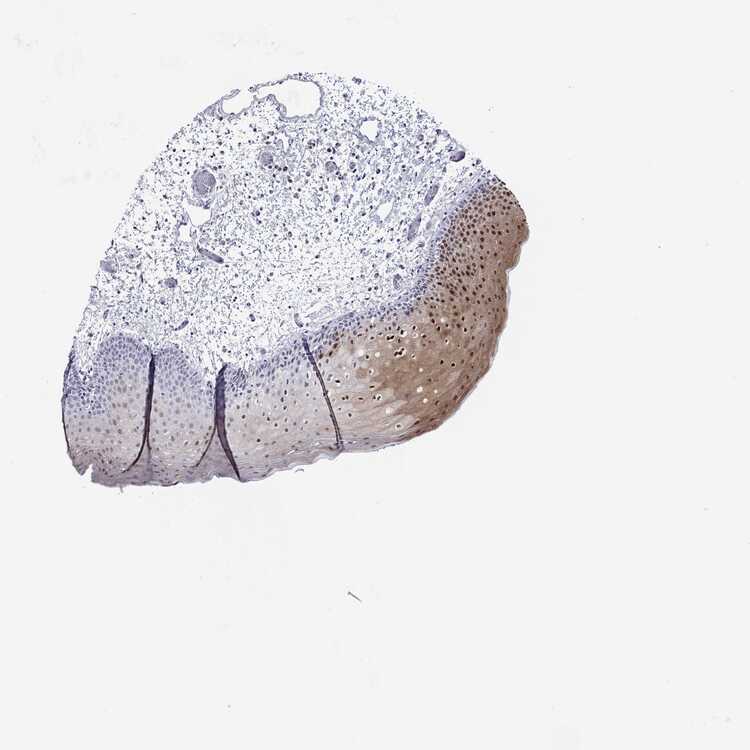

TISSUE PRIMARY DATA ORAL MUCOSA Show tissue menu

Oral mucosa

ORAL MUCOSA - Antibody stainingi

Antibody staining in the annotated cell types in the current human tissue is reported as not detected, low, medium, or high, based on conventional immunohistochemistry profiling in selected tissues. This score is based on the combination of the staining intensity and fraction of stained cells.

Each image is clickable and will lead to virtual microscopy that enables deeper exploration of all samples and also displays staining intensity scores, fraction scores and subcellular localization as well as patient and tissue information for each sample.

Antibody HPA048341Antibody HPA049988Antibody HPA055992Antibody CAB080099

Squamous epithelial cells LowLowLowMedium